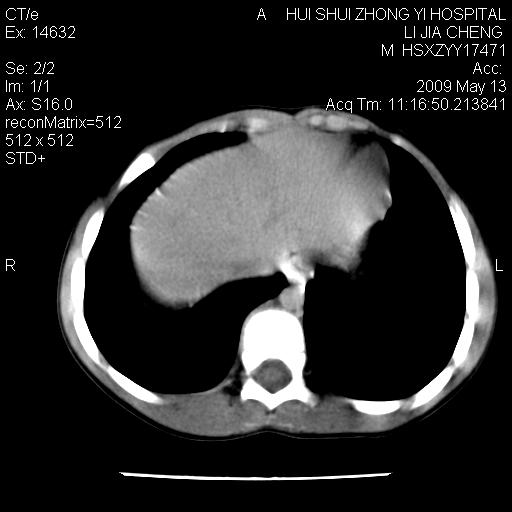

脂肪肉瘤可能性大,大血管边界不清,特别是腔静脉。不除外其他腹膜后肿瘤。

是不是有蛔虫哦,楼主图示块影前方肠管壁显著增厚,不除外慢性肠炎或肠壁占位,建议肠道准备后复查

来源于十二指肠水平部病变?建议行进一步检查。

是小肠,壁稍厚可能是肠腔未很好充盈所致,腹部ct扫描未见明显异常。